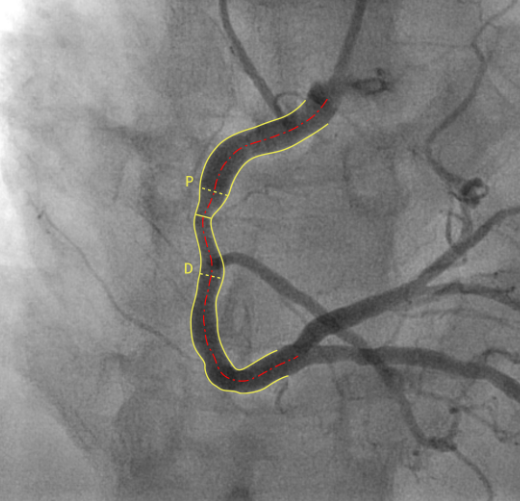

"우선 현재 혈관 형태를 파악합니다. 협착이 발생하면 원통형 혈관이 좁아지는 모양이 확인되는데 AI가 이 형태를 판독합니다. 혈관분할(Segmentation)과정입니다.

또 AI는 학습된 데이터를 통해 협착이 발생하지 않았을 경우의 혈관을 모델링합니다. 이후 정상이었을 혈관 모양과 현재 혈관 모양을 비교해 협착 정도를 측정합니다.